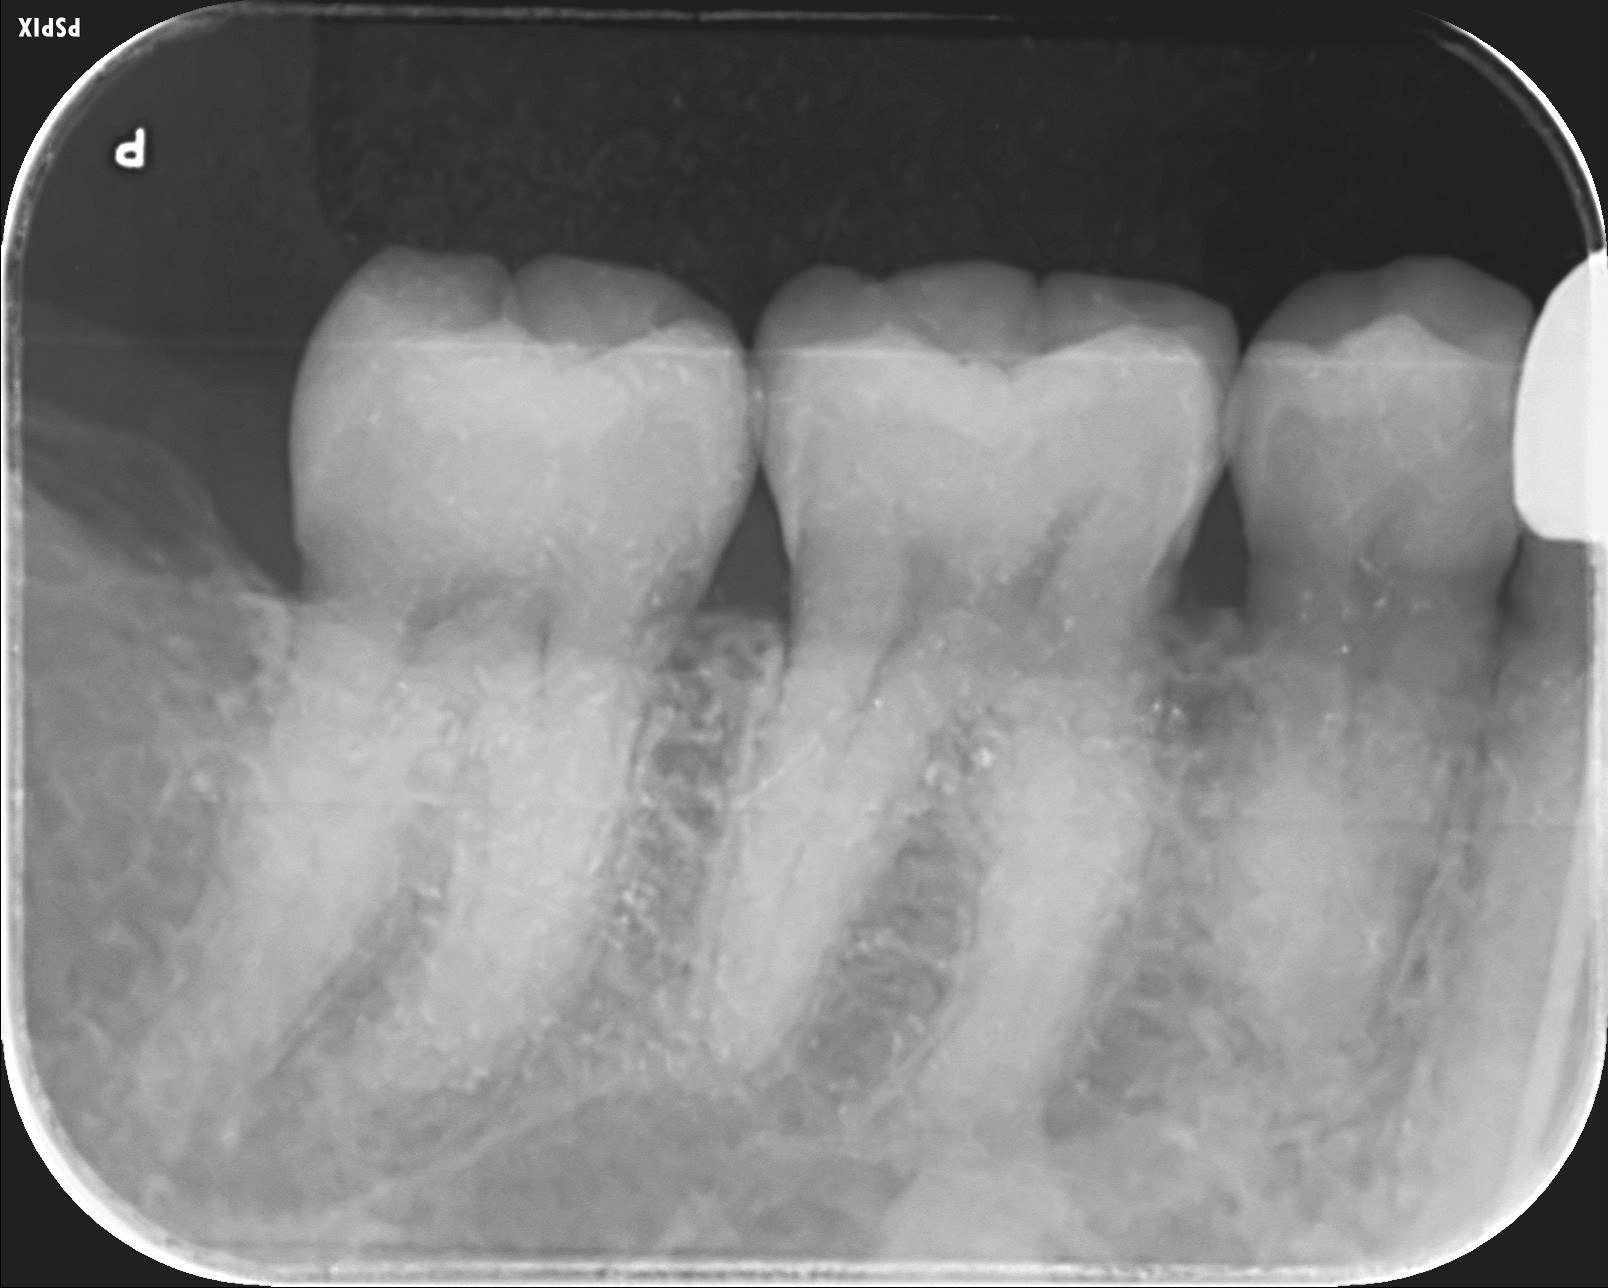

歯と歯の間の虫歯をだイレクトボンディングで治療しました。

X線写真で、段差なくピッタリ充填できているのがわかります。